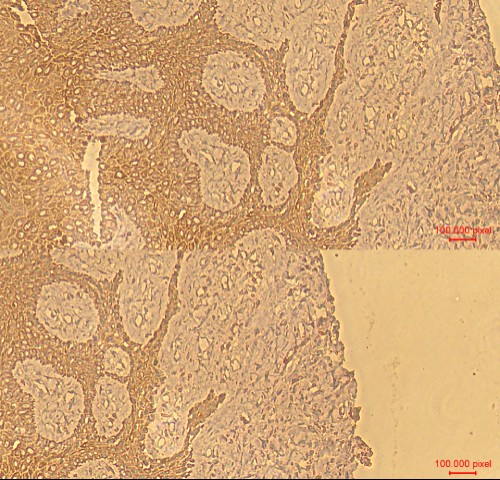

The Central Research Laboratory, Department of Research, Meenakshi Academy of Higher Education and Research (MAHER), successfully conducted a Three-Day Hands-on Workshop on Immunofluorescence and Immunohistochemistry from 23rd to 25rd July 2025 at No.12, Vembuliamman Koil Street, West K.K. Nagar, Chennai – 600 078.

The workshop was organized under the guidance of Dr. D. Nalini, Organizing Secretary, and featured dedicated hands-on sessions in Immunofluorescence on Day 1, followed by advanced training in Immunohistochemistry on Day 2 and Day 3. Participants gained in-depth practical knowledge and exposure to modern laboratory techniques, making it a highly interactive and impactful learning experience.